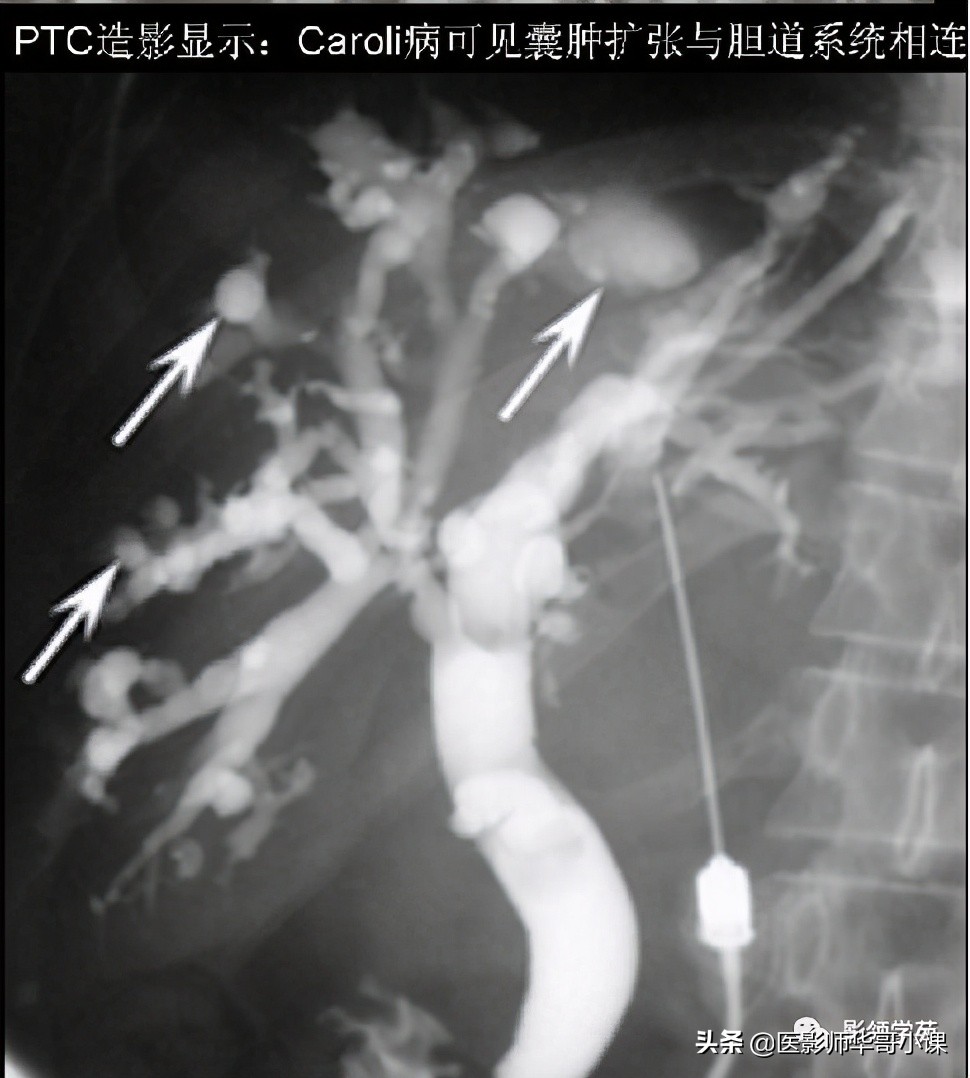

- 囊状扩张的胆管与胆树交通

- 部分囊状扩张的胆管腔内有门静脉分支(箭头)

- 经皮肝穿刺造影 (PTC):因PTC是有损伤性的检查,现临床上已较少应用。